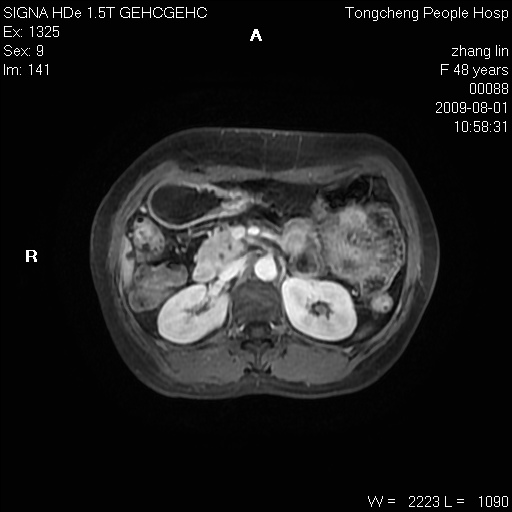

女,48岁。健康体检,彩超发现右肾占位性病变。平素健康。

临床诊断:右肾占位性病变,性质待定(囊肿?肿瘤?)。

上中腹部mr平扫+增强扫描,图像如下:

右肾上极见一类圆形病灶,t1wi呈等信号t2wi呈等高混杂信号,三期增强无强化,边界清---考虑囊肿出血。

同反相位均表现为等信号,病变无强化,考虑含蛋白的囊肿可能,弥散加权相或许有些帮助,

慢性胆囊炎